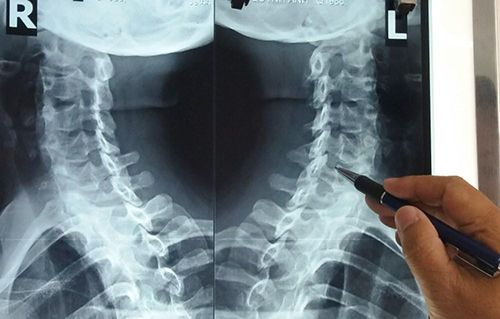

Đau nhức xương khớp là tình trạng nhiều người có thể gặp phải, nhất là mỗi khi thời tiết trở lạnh đột ngột. Đây có thể là triệu chứng của một bệnh lý xương khớp nào đó như thoái hóa cột sống, viêm khớp, thoát vị đĩa đệm, gai cột sống… Để hiểu rõ hơn về nguyên nhân, cách nhận biết cơn đau nhức đáng lo ngại mời các bạn tìm hiểu trong bài viết dưới đây!

Trong các khớp dễ thoái hóa tổn thương thì có khớp vai, khớp cột sống cổ, cột sống thắt lưng, khớp đầu gối, bàn chân, khớp háng, khuỷu tay… vậy có những bệnh lý nào có thể là nguyên nhân đằng sau gây ra những cơn đau nhức xương khớp này? Dưới đây là một số bệnh lý tiêu biểu nhất: